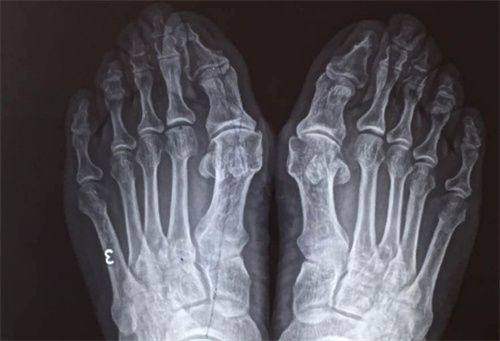

医学检验科和医学影像科为术前的诊断和评估提供了正确的数据和影像支持,帮助医生制定更加科学合理的治疗方案。